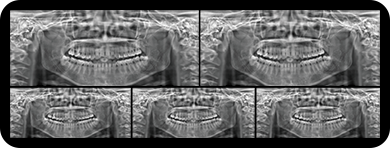

局部超清显示、 移动视野摄片

真人正侧位投影,实现CT成像区域无极可调

临床样片